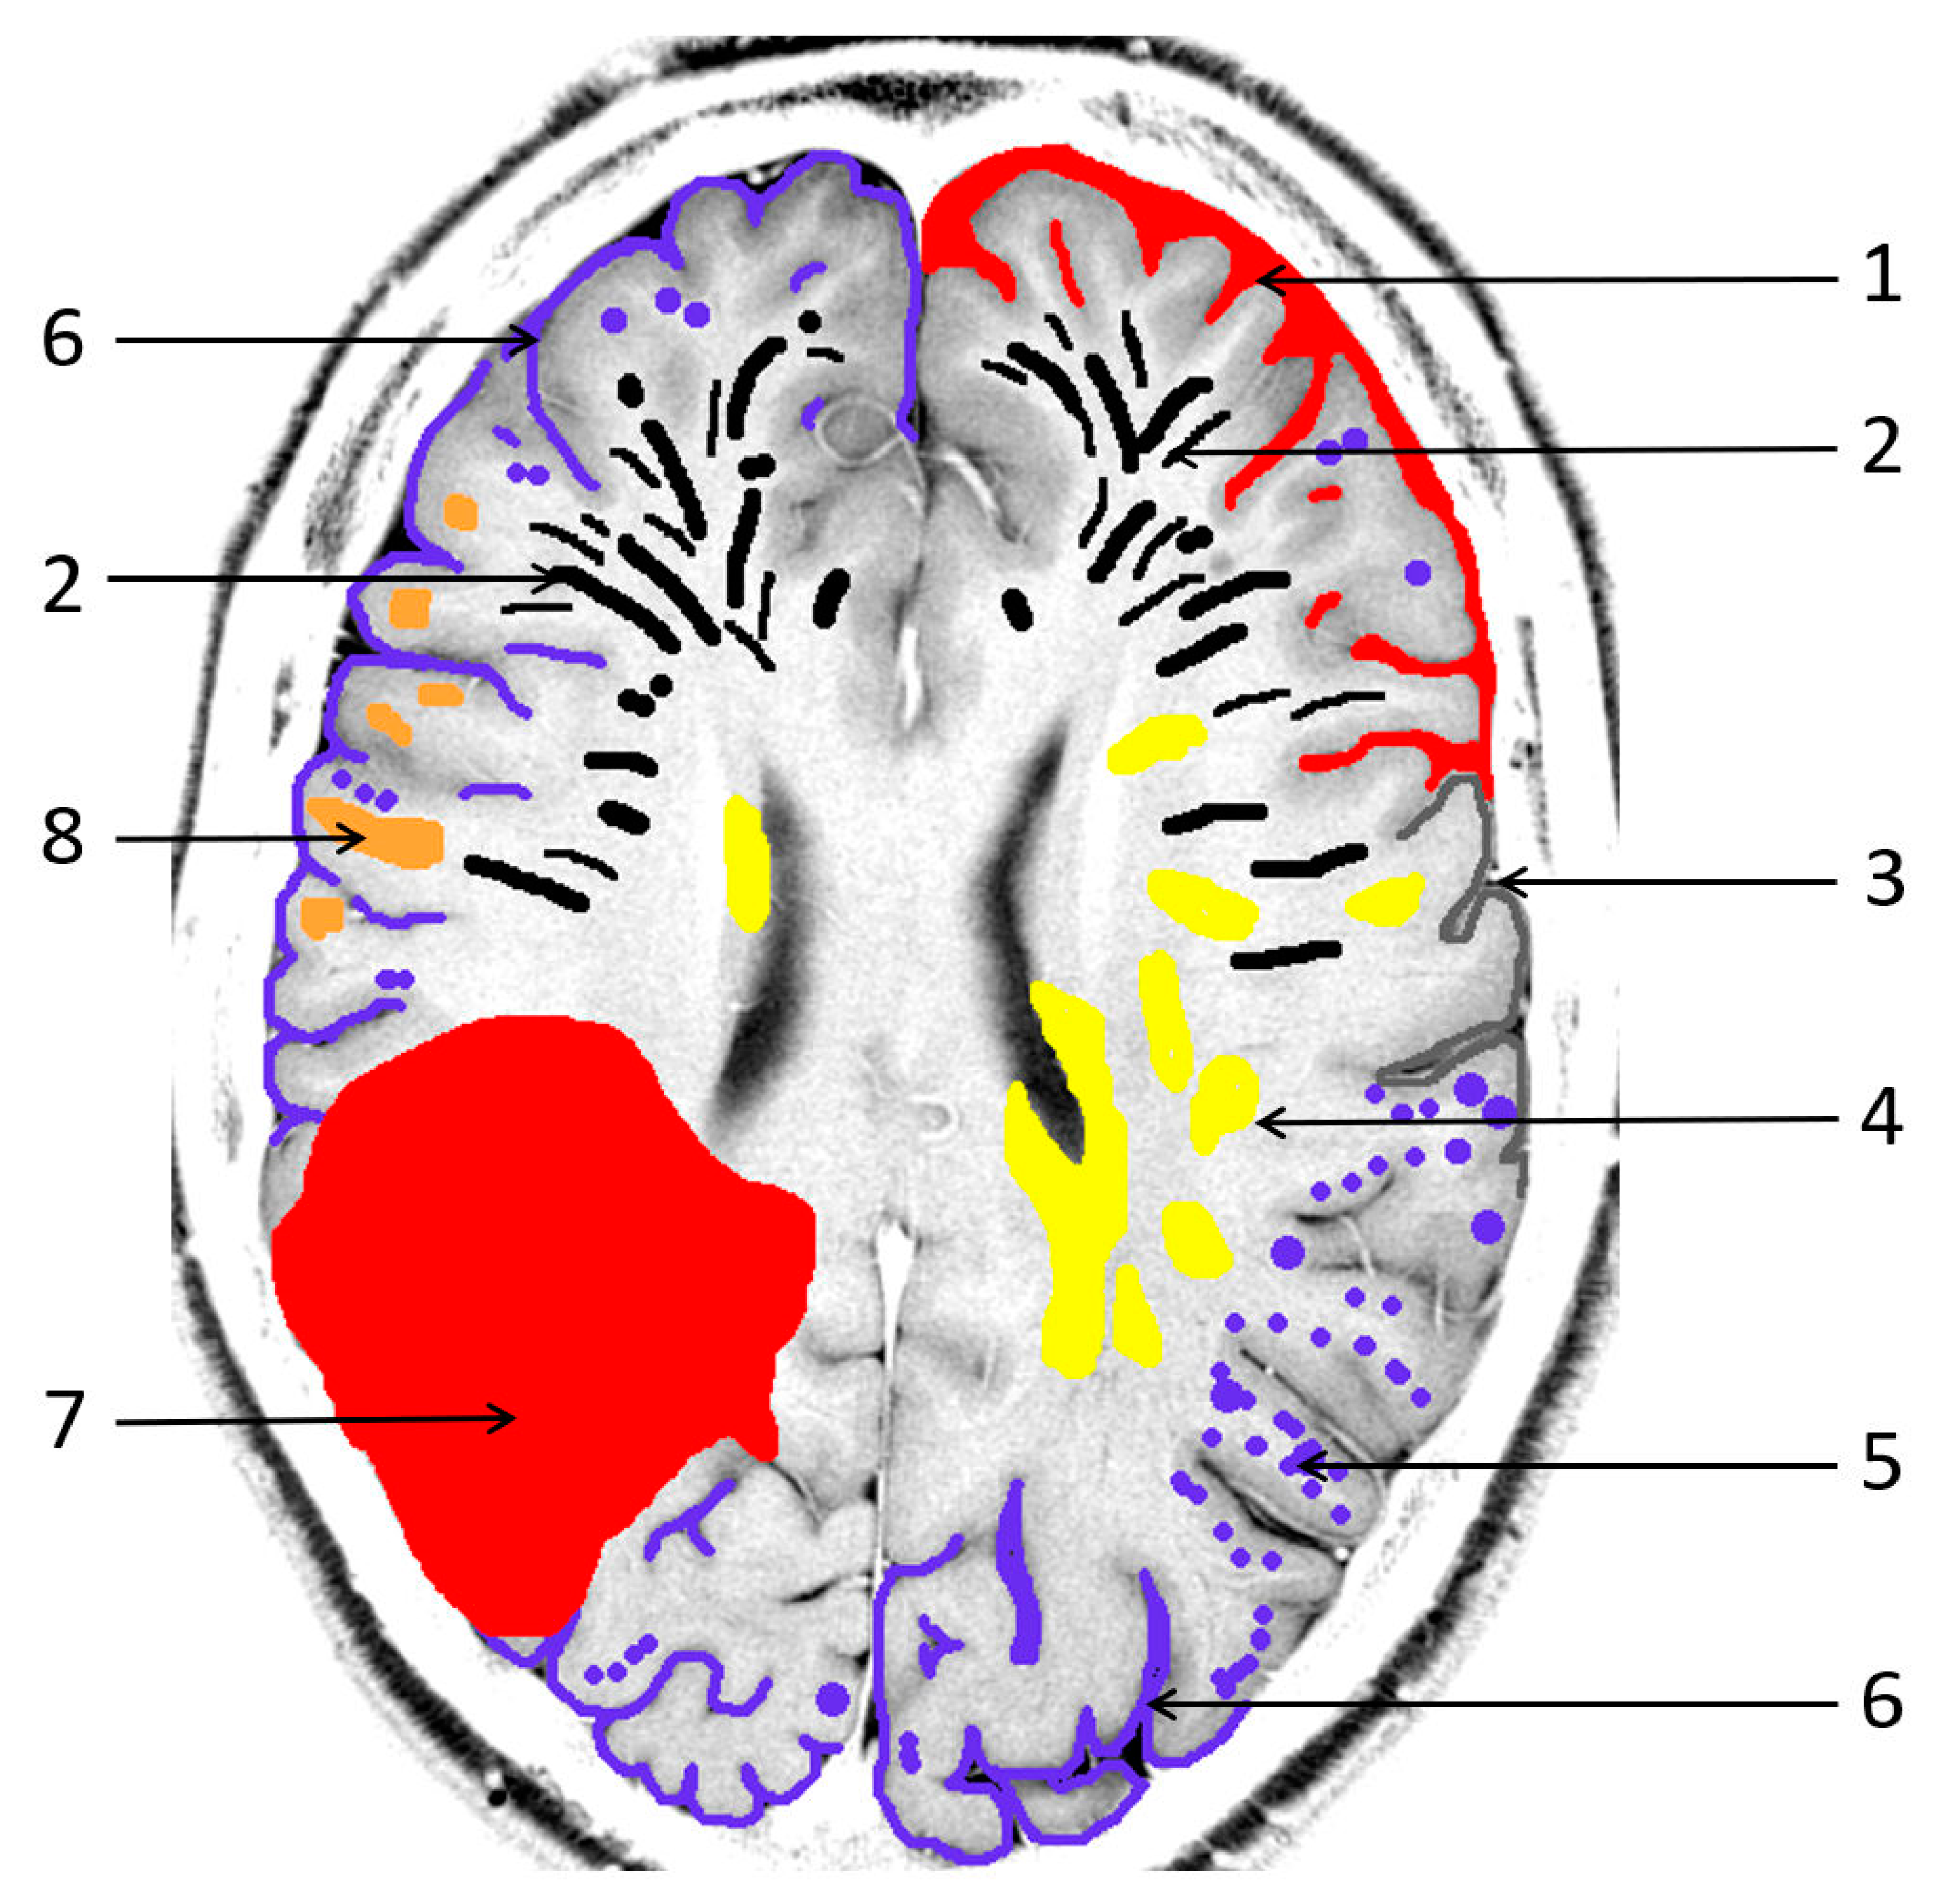

Figure 2.

Recurrent intracerebral hemorrhages (ICH) within 2 years in a 74-year-old man with a history of progressive cognitive impairment. The patient was on antihypertensive medication and a statin but had neither antithrombotic drugs nor anticoagulant therapy. The final diagnosis was new lobar ICB due to probable CAA in accordance with the 2.0 version of the Boston criteria [38]. Axial FLAIR (fluid attenuated inversion recovery) images (a–c) showing three ICHs at different time points parieto-occipital right ((a,d): arrow), temporal right ((b–e): arrow) and temporal left ((c,f): arrow); (d–f): susceptibility-weighted imaging (SWI; arrow) disclosing additional multiple microbleeds (MB) with temporal accentuation (d–f: arrowhead); MRI 1.5 T Siemens AREA.

1. Intracerebral hemorrhages (ICH) are the most common manifestation of CAA, with lobar ICH being the most prevalent [1,3,18]. These are associated with a high risk of recurrence, particularly in the temporoparietal and occipital regions (Figure 2) [1,18]. Histopathological analyses in post-mortem studies have demonstrated subcortical white matter changes in a multispot pattern and in cortical infarcts due to CAA complete replacement of the vascular smooth cell layer by Aß deposits (Vonsattel grade 2) [48,49,50]. Moreover, individual vessels associated with ICH specimens showed complete vascular remodeling in the form of Vonsattel grade 3–4 [48,49,50,51,52,53]. While APOE-E4 has been identified as risk factor for recurrent CAA-associated bleeding, APOE-E2 is the primary risk factor for AD and CAA, often leading to a more severe clinical course [3,18,24,25]. Neuroimaging biomarkers associated with the highest risk of further ICH in patients suffering from previous CAA-related ICH are (a) a higher number of cerebral microbleeds (cMB), (b) disseminated or multifocal cSS and (c) the development of new cSS on follow-up MRI. Therefore, ICH prediction also has an impact on the risk-versus-benefit calculation of antithrombotic treatment in patients with indications such as atrial fibrillation [51,52]. Restarting of platelet aggregation inhibitors, i.e., acetylsalicylic acid, seems to be a reasonable safe option following ICH. However, a clear and ambiguous individual indication should be a requirement for anticoagulant therapy in these patients. To date, the extent to which patients with CAA-associated ICH will benefit from anticoagulation in nonvalvular atrial fibrillation regarding the prevention of stroke (ischemia versus hemorrhage) has not been conclusively clarified [40,51].

2. Cortical and subcortical microbleeds (MB), which have been identified as a risk factor for lobar ICH and ischemia, have also been associated with cognitive impairment [38,53,54,55]. In contrast to hypertensive microangiopathy caused by lipohyalinosis, which typically affects the basal ganglia, thalamus, pons and cerebellum [55,56,57,58,59,60], MB are generally absent in these regions in CAA [38,54,61]. Due to the neurodegenerative and cerebrovascular processes associated with Aß deposits, MBs are preferentially localized in the parieto-occipital regions in both CAA and AD (Figure 1, Figure 2 and Figure 3) [3,19,53,54,61].